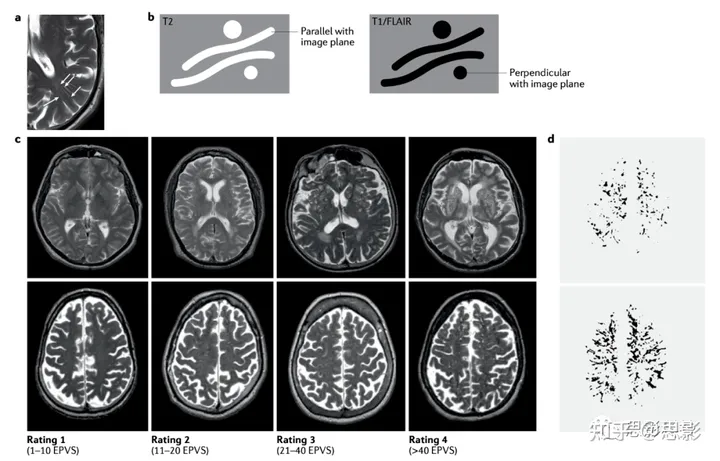

人们认为,血管周围间隙(包括潜在通道)以某种形式包围着脑部的小动脉、毛细血管和小静脉。在脑MRI上可见的脑实质内的血管周围间隙垂直于脑表面,与穿行血管平行且在空间上相关。因此,有理由相信这些可见的血管周围间隙与穿行血管有关。沿着图像平面运行的血管周围间隙呈线状,垂直于图像平面的血管周围间隙呈点状(图1)。

图1 人类通过磁共振成像(MRI)观察到的脑周血管间隙。

a | T2加权MRI上显示的枕颞区典型的血管周围间隙。这些间隙呈细白线状,从侧脑室延伸到皮质(箭头所示)。b | T2加权、T1加权和液体衰减反转恢复(FLAIR)图像上血管周围间隙的示意表示。c | T2加权MRI扫描显示基底节(顶行)和半卵圆中心(底行)血管周围间隙可见程度不同。底部显示扩张血管周围间隙(EPVS)的视觉评分(1-4)。d | 轴向视图显示通过计算识别的中度(顶部)和严重(底部)血管周围间隙。

迄今为止,几乎所有关于血管周围间隙及其关联的MRI研究都依赖于视觉评分进行定量,因为直到最近,计算机图像分析方法还没有足够先进到能够量化这些小结构(图1)。过去18年里,已经发展出了几种视觉评分方法,但所有这些方法都采用类似的方法,量化类似脑区的血管周围间隙。在扫描切片上手动计数血管周围间隙耗时太长,特别是在大型研究中,因此大多数评分提供了基于解剖学定义区域内血管周围间隙近似数量的定性估计。因此,在定义的脑扫描切片上,基底节区域内少于10个血管周围间隙会产生1分,11-20个产生2分,21-40个产生3分,>40个产生4分(ref.43)。这些评分在临床研究中使用快速且实用,并具有良好的可靠性和重复性,因此已经应用于许多个体研究,其中一些涉及数千人。然而,这种定性评分相对不敏感,受到地板效应和天花板效应的限制。

等向性3D MRI采集和计算机图像分析方法的进步使得血管周围间隙的计算定量成为可能。这些方法需要进一步测试以确认其价值,但可能会提高对变化的敏感性。一些方法除了数量之外还能量化血管周围间隙的几个特征(例如,血管周围间隙的总体积、单个大小、长度、宽度、球形度、方向性和与其他结构的邻近性),并生成与组织完整性相关的空间度量。使用这些方法对人类进行的早期研究已经显示出视觉评分和计算血管周围间隙的数量、体积和单个大小之间的高度一致性(图1)。